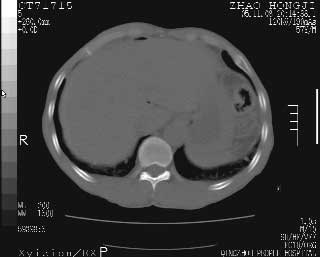

临床资料:男性,57岁,上腹部疼痛并5天,突然加重并延及全腹伴恶心5小时入院。胰淀粉酶化验在正常范围。检查:腹肌紧张,全腹压痛、反跳痛,尤以右上腹部为著。肠鸣音减低。血常规:wbc14.6x10/9, n:11.3x10/9 ,血压:135/90mmhg. 胸部透视:腹部肠腔轻度张气,未见其它异常改变。

肝右前缘少量积气,其他未见明显异常.考虑上消化道穿孔.

小网膜囊积气液,胃壁僵硬。考虑胃穿孔。

小膜网膜积液,肝缘气腹征,上消化道穿孔。

胰腺形态规则,胰周脂肪间隙清晰,结合临床可排除急性胰腺炎

从图提示我同意空腔脏器穿孔的诊断,来源肠道{由于病程较短,故没能见到肠系膜聚局的征象}。

肝缘见少许气体,胰尾部见少许气体包饶(蓝色圈),12指肠上部或球部邻近胆囊周边也可见少许气体影(黄色圈),并忖托出胆囊壁,12指肠远段肠道内未见明显气体(白色箭)。

肝脏前缘见少量积气、胰尾部见少许气体包饶,肾前筋膜未见增厚,临床淀粉酶不高,意见:上消化道穿孔。

消化道穿孔。12指肠球部周和胰周积气考虑12指肠穿孔可能性大。

入院3小时后行剖腹探查术,见腹腔内大量脓性混浊液约1000ml,十二指肠球部溃疡穿孔,溃疡面约2.5x2cm,穿孔直径约0.6cm。胃内容物外益,周围组织炎性水肿明显。行十二指肠穿孔修补术。术后诊断:

1、十二指肠溃疡穿孔

2、弥漫性腹膜炎

对于少量的腹腔游离气体,ct检查较普通透视有绝对的优势,它不仅可以看到肝脏前上缘的气体,而且还能够看到小网膜区的游离气体。从而可以肯定诊断。各位分析战友的很好,感谢大家的参入!